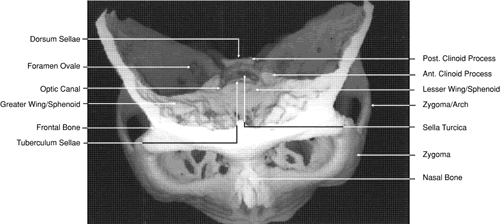

Fig. 29. A. Axial computed tomography soft tissue image at the level of the base of skull. B. Axial computed tomography bone window image at the level of the base of skull.

The globe is shown in Figure 12. The orbit and periorbital structures are shown in Figures 13 through 16, and the optic canal is shown in Figures 17 through 26. The cavernous sinus and optic chiasm are shown in Figures 27 and 28, and the posterior visual pathway and cranial nerves are shown in Figures 29 through 33.